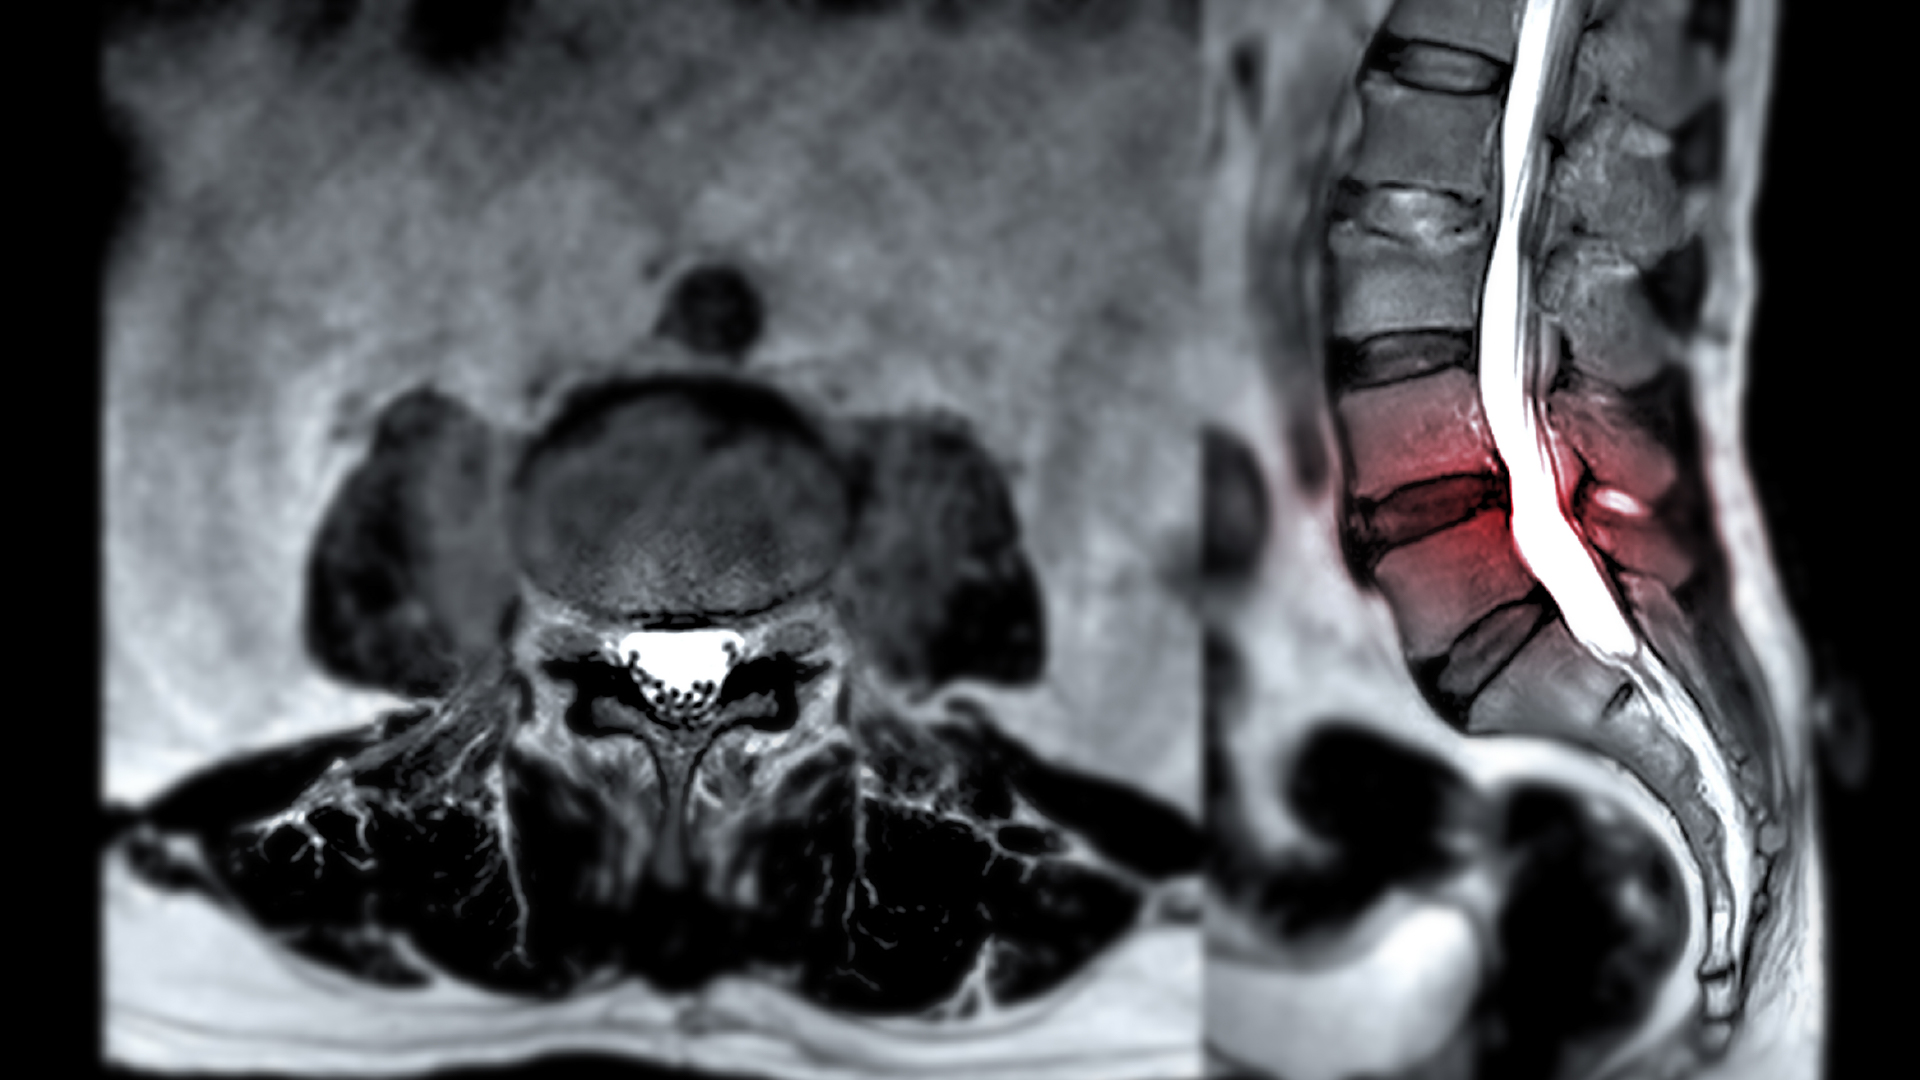

MRI เป็นเทคโนโลยีตรวจวินิจฉัยด้วยคลื่นแม่เหล็ก ไม่ใช่รังสี จึงปลอดภัยต่อร่างกาย ช่วยให้เห็นภาพโครงสร้างภายในอย่างละเอียด ทั้งเนื้อเยื่อ เส้นประสาท หมอนรองกระดูก และกระดูกสันหลัง โดยมีความแม่นยำสูงกว่า 97% ในการตรวจหาความผิดปกติของระบบกระดูกและเส้นประสาท

อย่างไรก็ตาม การวินิจฉัยที่แม่นยำที่สุดมักต้องใช้ MRI ควบคู่กับ X-ray เพื่อให้แพทย์เห็นภาพรวมของแนวกระดูก ความโค้ง หรือการเคลื่อนของข้อ ซึ่งช่วยให้สามารถวิเคราะห์อาการได้ครอบคลุมยิ่งขึ้น

ใช้สนามแม่เหล็กแรงสูง ให้ภาพคมชัดระดับ 3 มิติ ครอบคลุมทั้งเนื้อเยื่อและกระดูก เหมาะกับผู้ที่ต้องการตรวจเชิงลึก เช่น หมอนรองกระดูกปลิ้น หรือโพรงประสาทตีบ การตรวจใช้เวลาประมาณ 30 นาที และแพทย์สามารถวิเคราะห์ผลได้ทันที